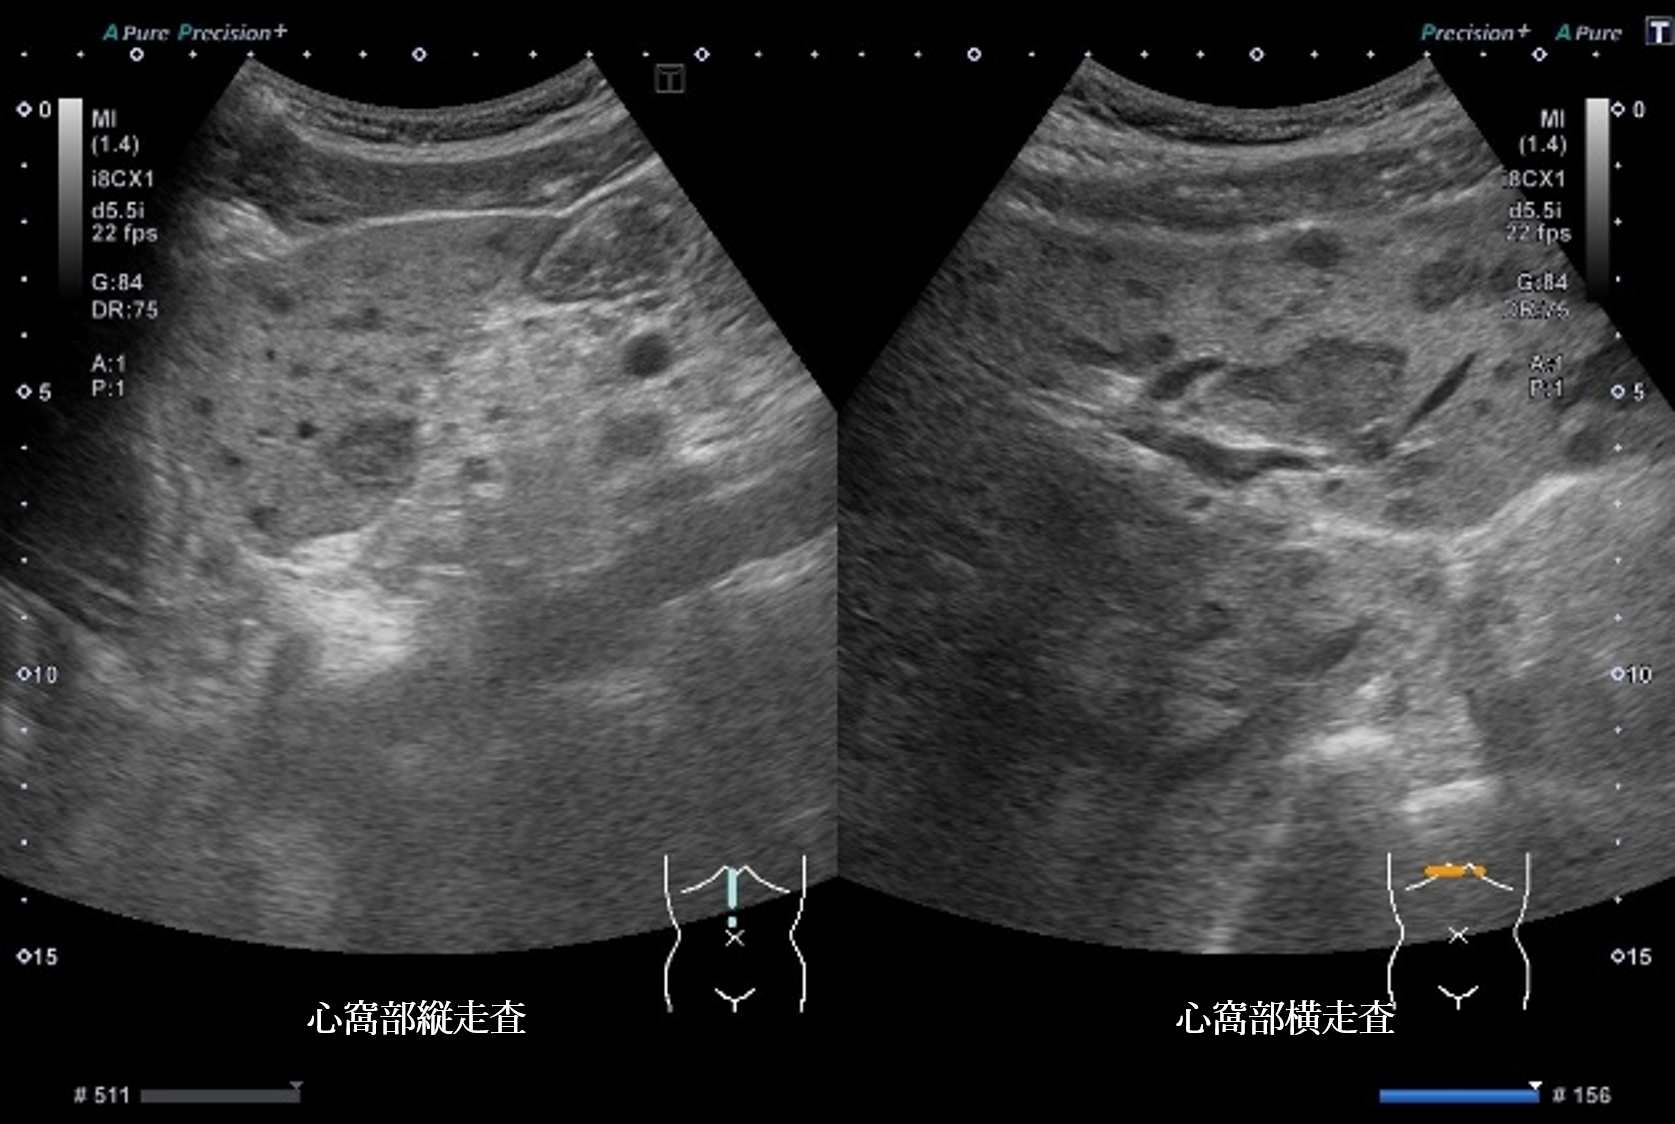

静止画4枚、動画1枚を示す。

腹部超音波画像 画像1(No16-17_1)画像2(No16-17_2)画像3(No16-17_3)画像4(No16-17_4)

超音波所見より正しいのはどれか

① 肝全体に内部無エコーな腫瘤性病変を多数認める

② 肝全体に腫瘤性病変が多数みられ、辺縁低エコー帯を認める

③ 肝実質は粗雑不均質に観察され、明らかな腫瘤性病変は指摘できない

④ 肝全体に腫瘤性病変が多数みられ、腫瘤内部はモザイクパターンを呈する

⑤ 肝全体に腫瘤性病変が多数みられ、腫瘤辺縁にリング状高エコー像を認める